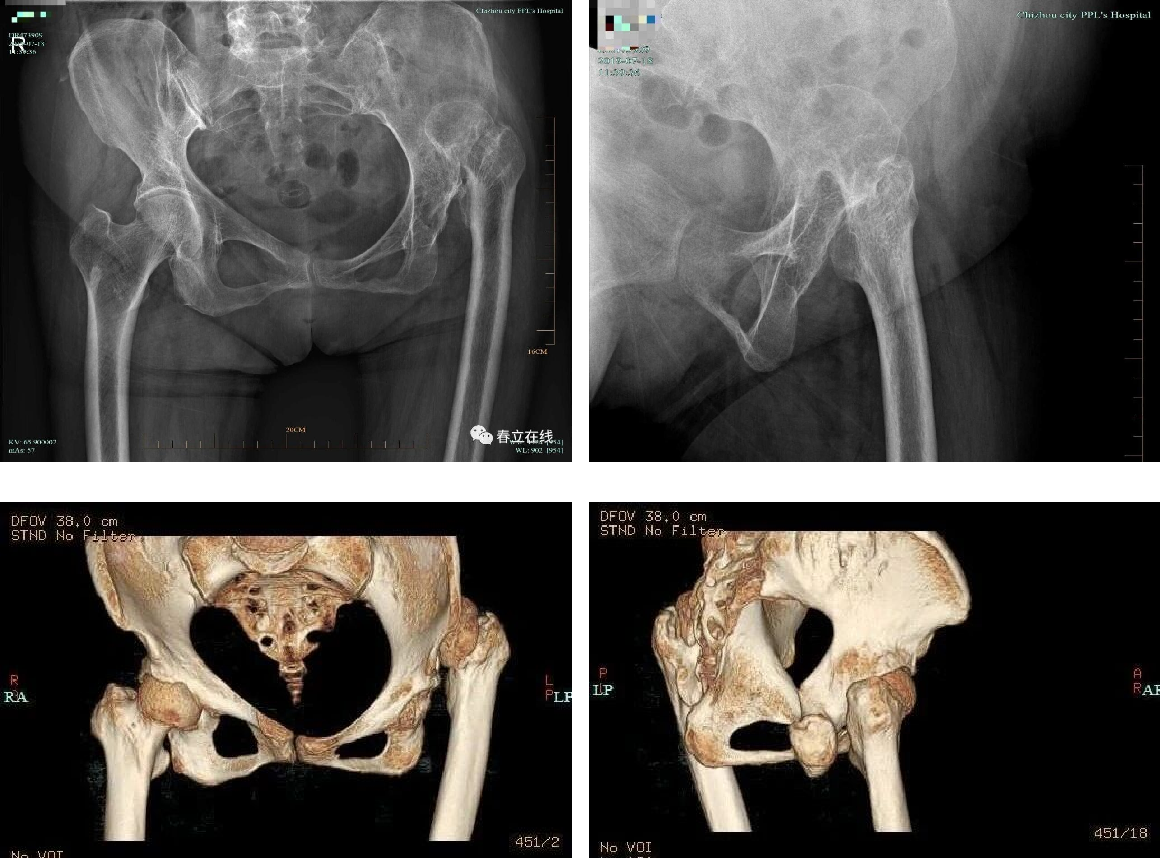

The patient is diagnosed with developmental dysplasia of the left hip (DDH), presenting with hip claudication for 50 years, left hip pain for 20 years, and symptom exacerbation over the past year. The condition has impaired her walking ability and affected daily life and physical labor, and she is scheduled to undergo left total hip arthroplasty.

Preoperative X-ray and CT scan